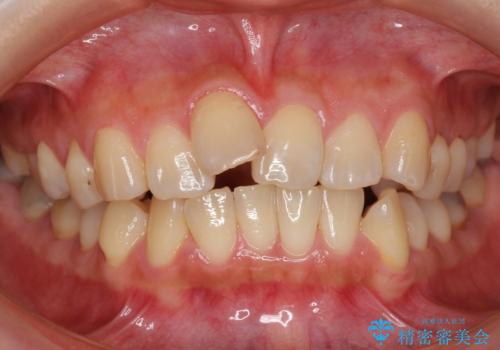

前歯を引っ込めたい 歯を抜かずにマウスピースで

- 前歯の突出を主訴に来院。

上の奥歯を後ろに下げて治療をしました。

矯正用のミニスクリューを使用しています。